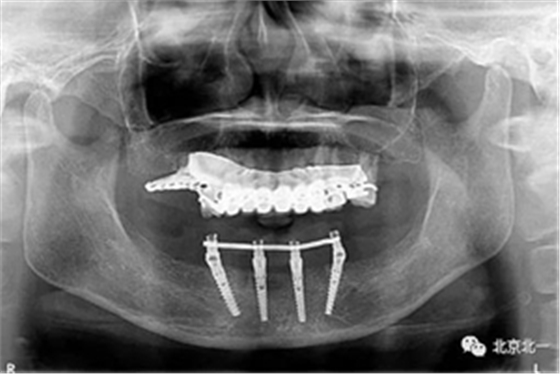

圖十五:術(shù)后即刻拍X片

圖十七:拍X片確認無誤差

圖二十一:半年后復(fù)查X片

圖二十二:2015年到2016年復(fù)查時X片 ,有圖有真相

圖二十四:2017年11月復(fù)查時照片,植體很穩(wěn)定, 無骨吸收。